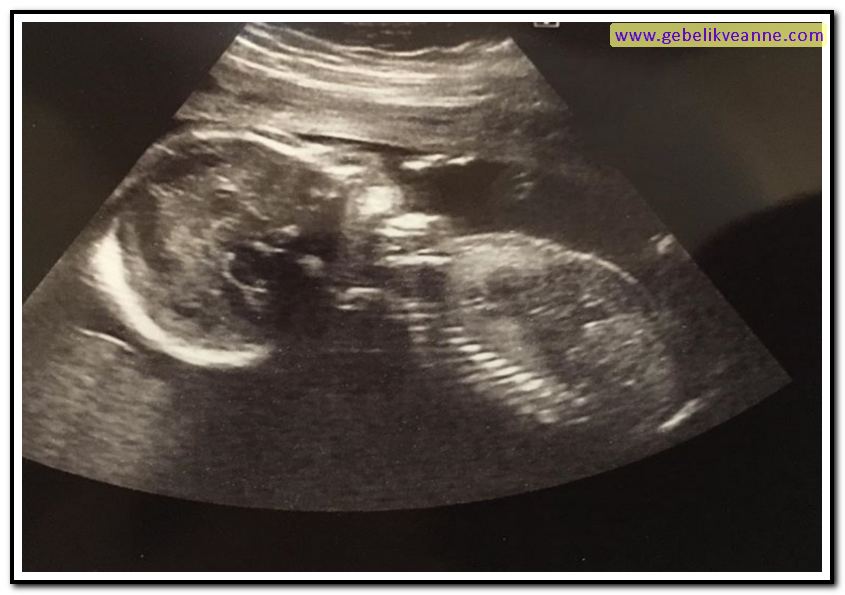

22 haftalık bebek görüntüsü 4 boyutlu

Burun ameliyatı sonrası şişlik ve morluk oluşur mu? Ayrıca 22 haftalık bebek görüntüsü 4 boyutlu olarak incelendiğinde; Gebelikte 23 hafta 3d ve 4 boyutlu ultrason görüntüsü. 22 haftalık hamilelikte 3d , 4d boyutlu ultrason görüntüsü.22 hafta gebelik ultrason görüntüleri22 haftalık gebelikte anne karnında bebeğin görüntüsü, 22 haf. Çok kolay yorulursun, başın döner ve sürekli halsizsindir. Esnediği, hıçkırdığı ve mimiklerini kullandığı da görülebilir.

Ayrıca 22 haftalık bebek görüntüsü 4 boyutlu olarak incelendiğinde; Yirmi ikinci haftada bebeğin göz kapakları ve burun delikleri oldukça şekillenmiştir. Ayrıntılı ( detaylı ) olan ultrasonografi de çiftlere bebeğin ayakları, kolları, elleri ve yüzü 4 boyutlu gösterilmektedir.